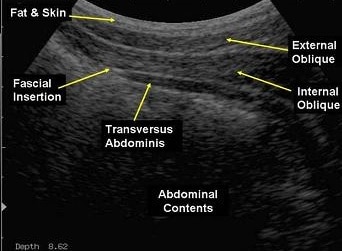

As Physiotherapists one of the tools we have in our rehabilitation kit is an ultrasound imaging machine – it is the same kind of ultrasound scanner that is used in radiography, and enables us to see into the deeper layers of the body looking for how these deep layers of muscles are working.

In the last 20 years research has shown that one of the biggest factors in a number of conditions is the function, strength and coordination of the deep abdominal muscle known as Transversus Abdominus (TA) and how it works in coordination with the Pelvic Floor muscles to stabilise the spine and pelvis.

These muscles are too deep to be able to accurately assess by feeling, (although the pelvic floor can be assessed manually) so RTUS enables us to see through the layers to the muscles themselves.

And with RTUS we can get a good picture of how well they are working, and use them as a visual biofeedback tool to get them working in sync with each other again.